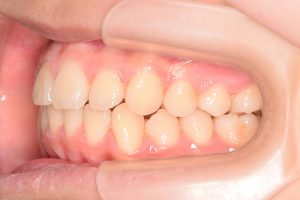

右側

0000000003

0000000024

0000000075

1期治療開始時(2024年3月)

2期治療開始時(2024年11月)

保定開始時(2025年1月)の写真です。